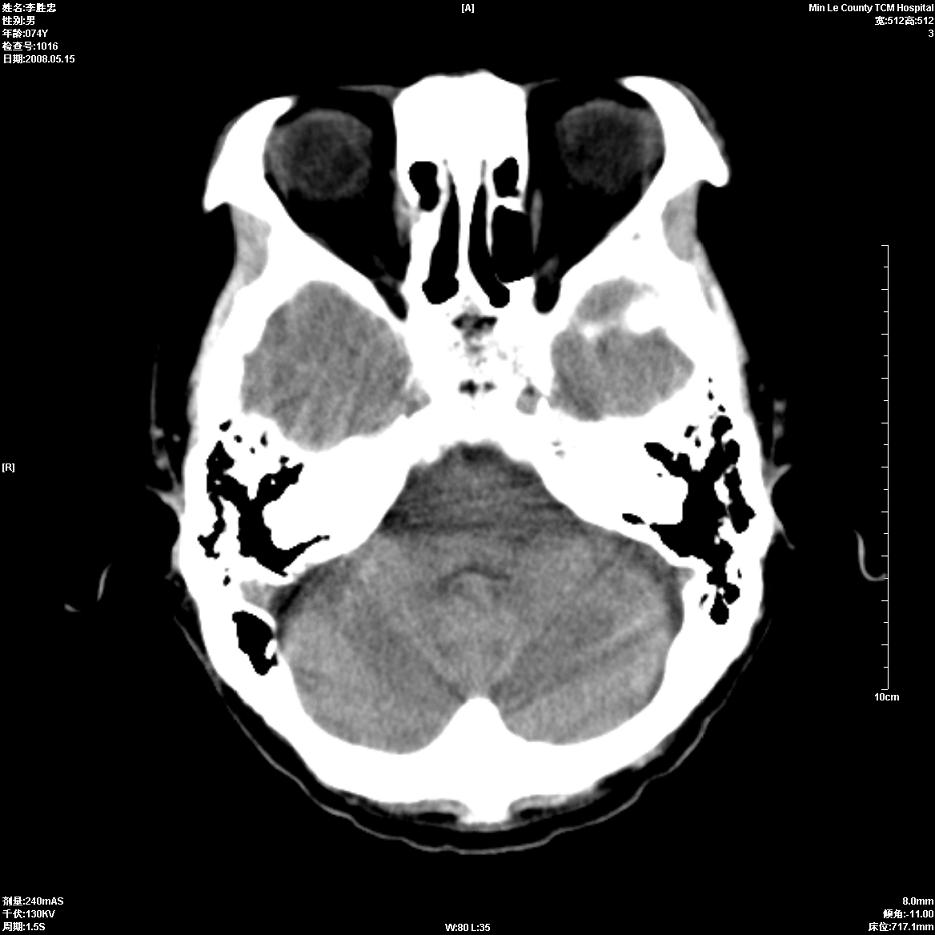

以下是引用hhcckk在2008-5-30 14:26:00的发言:[br]病灶跨中线,有占位效应,强化不明显,考虑胼胝体区低级别的星形细胞瘤可能性大,建议mr检查